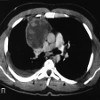

КТ средостения. Многослойная рентгенограмма средостенного пространства, которая обладает высоким разрешением и способностью строить трехмерные реконструкции изображений КТ. Область исследования включает трахею, пищевод, тимус, сердце, брахиоцефальные вены, часть верхней полой вены, нисходящую грудную аорту и дугу, легочные артерии и вены, лимфатические протоки и лимфатические узлы, нервные стволы и сплетение. Компьютерная томография средостения назначается при подозрении на первичное образование опухоли или метастазы в органы средостения, саркоидоз, лимфогранулематоз, медиастинит, повреждение грудного протока Если необходимо более полное обследование лимфатических узлов или объема средостения, исследование проводится с внутривенным контрастом болюса.

КТ средостения